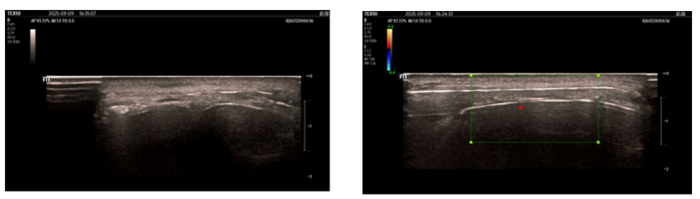

伍少玲教授、许珍医师为李先生实施了手术。在超声影像的实时引导下,电极被精准放置于左侧眶上孔周围——这里是三叉神经 V1 支(眼神经)的关键走行区域,也是刺激大脑意识中枢的重要靶点。术中超声清晰显示,电极正位于左侧眶上孔正上方的神经走行区;同时,通过体外程控调节电流,当场诱发了李先生眶周肌肉(眼轮匝肌、提上睑肌)的收缩,这意味着刺激信号已成功传递到神经。术后复查头颅正侧位片进一步确认:电极位置准确,无偏移。

超声下可见电极放置于左侧眶上孔正上方三叉神经V1支走行区域